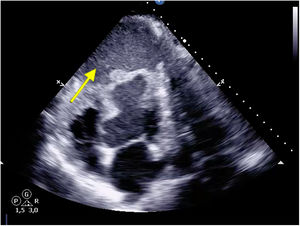

A 49-year-old male was admitted with a SCAI D cardiogenic shock following a 12-day history of non-ST-elevation acute coronary syndrome, not revascularized in his country of origin, complicated by intramyocardial dissection, resulting in a contained apical posterior hematoma (Fig. 1, yellow arrow), hemodynamic instability, and severe biventricular dysfunction requiring veno-Arterial extracorporeal membrane oxygenation (ECMO) as a bridge therapy to heart transplantation.